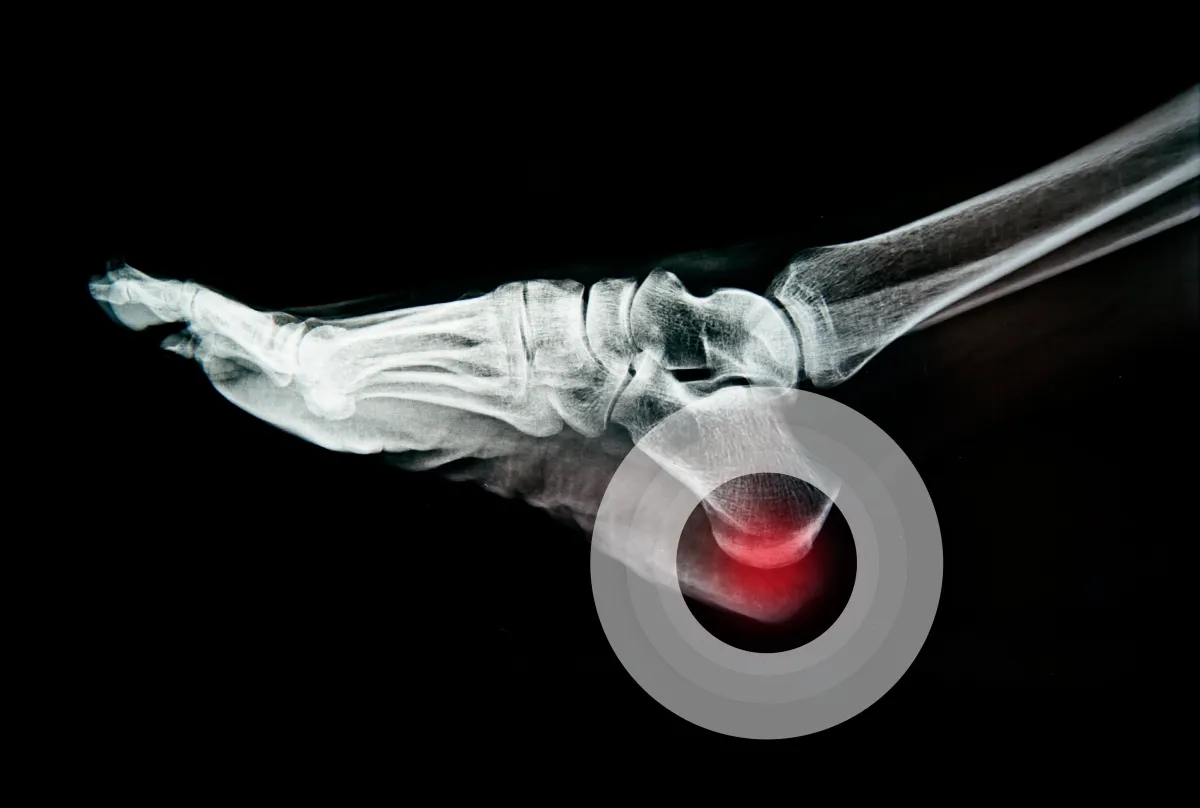

Help to diagnose the underlying cause of your symptoms

Long-term pain relief

Biomechanical Examination

gait analysis

Foot Mobilisation Therapy Evaluation